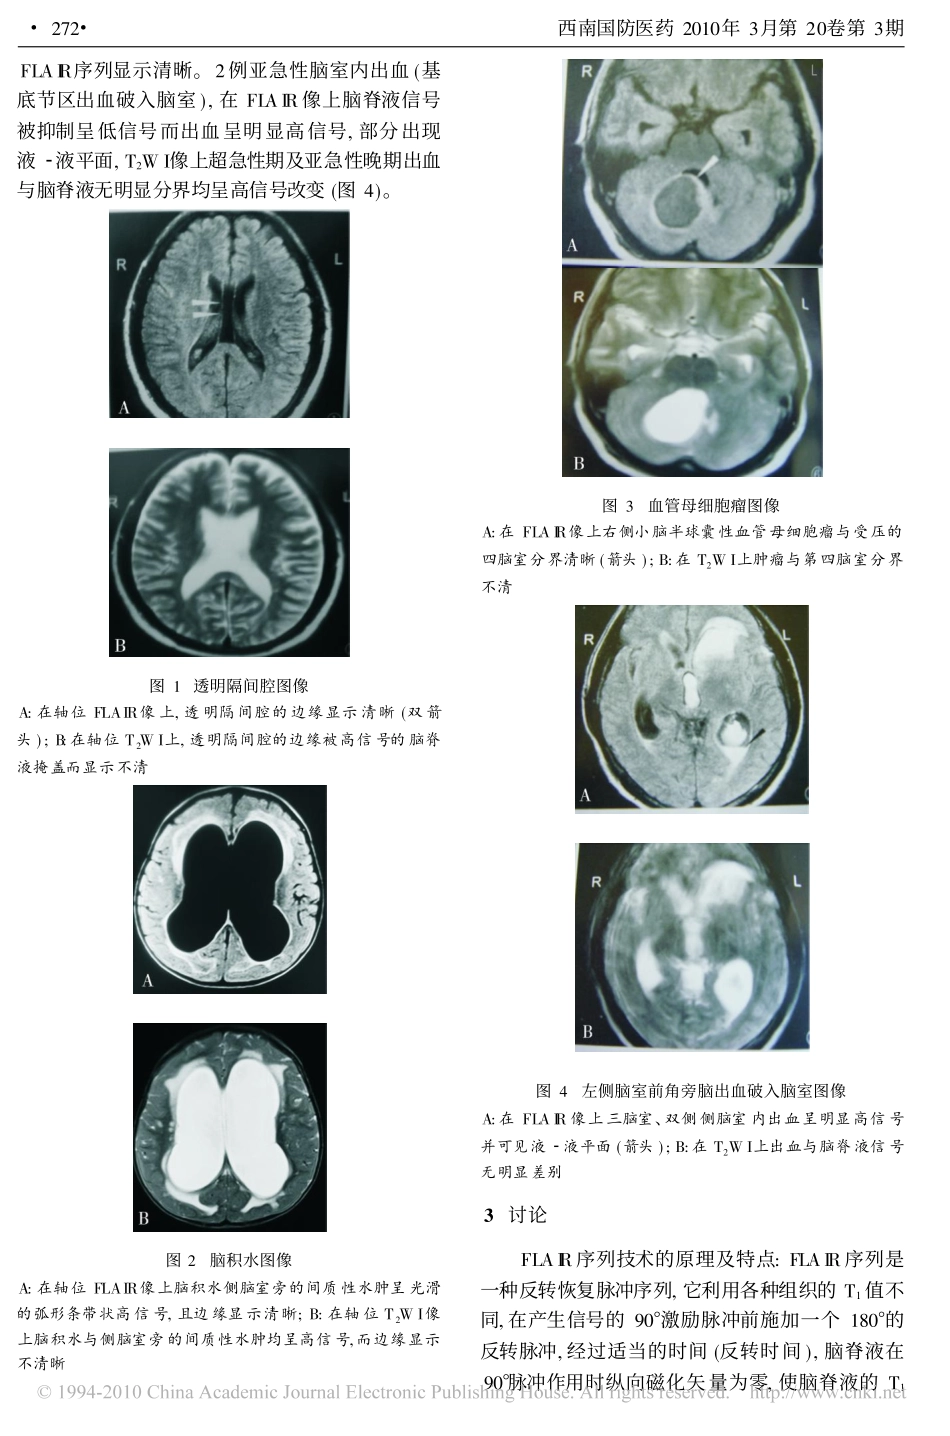

磁共振FLAIR序列在颅脑病变中的应用��作者单位:661600云南开远,解放军59医院医学影像科赵�邦,胡茂益[摘要]�目的�探讨液体衰减反转恢复(FLAIR)序列在颅内病变诊断中的应用价值。方法�对88例患者均行FLAIR序列和FSE�T2WI检查,比较两种序列对病灶的显示能力。结果�88例中,透明隔间腔5例,交通性脑积水6例,梗阻性脑积水10例,室管膜瘤2例,转移瘤2例,胶质细胞瘤5例,脑膜瘤5例,亚急性脑室内出血(基底节区出血破入脑室)2例,慢性硬膜下血肿2例,侧脑室内囊肿1例,脑白质脱髓鞘疾病20例,基底节区梗死15例,血管母细胞瘤5例,脑囊虫病3例,脑炎5例。以上疾病的病灶,在FLAIR序列上均能显示,并可清晰显示病灶边界;但在T2WI像上虽可显示病灶,但边界不清晰,难以清晰显示病灶边缘与周围组织关系。结论�FLAIR序列能够抑制脑脊液的信号,提高脑室内、脑室旁病灶的对比度,对脑室旁病灶、尤其是脑室内病变的显示较FSE�T2WI清晰。[关键词]�磁共振成像;液体衰减反转恢复序列;颅脑中图分类号�R651.11��文献标识码�A文章编号�1004�0188(2010)03�0271�03��do:i10.3969/.jissn.1004�0188.2010.03.013��在目前的影像学检查中,MRI已成为准确地显示解剖结构和反应组织病理特征的一种重要检查手段之一。由于其良好的空间分辨率、无骨伪影及多参数成像的特点,在中枢神经系统疾病,尤其在颅脑病变诊断中的价值尤为突出。笔者收集我院MR室2009年1~7月88例颅脑病变患者的MR影像资料,对同一病例相同层面的T2WI与FLAIR序列图像进行比较,探讨FLAIR序列在颅脑病变、特别是脑室系统疾病中的MR表现及应用价值。1�资料与方法1.1�病例资料�88例受检者中,男48例,女40例,年龄15~83岁。其中透明隔间腔5例,交通性脑积水6例,梗阻性脑积水10例,室管膜瘤2例,转移瘤2例,胶质细胞瘤5例(手术病理证实),脑膜瘤5例,亚急性脑室内出血(基底节区出血破入脑室,CT证实)2例,慢性硬膜下血肿2例,侧脑室内囊肿1例,脑白质脱髓鞘疾病20例,基底节区梗死15例,血管母细胞瘤5例,脑囊虫病3例,脑炎5例。1.2�影像学检查�使用德国SIEMENS�0.35T永磁型磁共振成像仪,依次进行SE�T1WI、FSE�T2WI和FLAIR序列扫描。SE�T1WI的扫描参数:TR/TE=20/8.9ms;FSE�T2WI的扫描参数:TR/TE=4720/108ms,采集次数为4,矩阵为256�256,回波为1;FLAIR的扫描参数:TR/TE/TI=7050/85.0/1900ms,采集次数为2,矩阵为512�512,回波为1。1.3�资料分析方法�由MRI诊断医师2人(主治医师)对上述88个病例的MRI资料进行对比分析(取相同病人同一层面的FLAIR序列图像与T2加权图像)。结果有78例病变2人均认为FLAIR序列较T2WI序列图像边缘显示清楚,占88.6%;8例病变2人均认为两者图像相当,占9.1%;2例病变1人认为FLAIR序列较T2WI序列图像好,1人认为FLAIR图像较T2WI稍差。原因:1例因病人扫描时躁动伪影较大而影响观察,重新扫描后均认为病灶边缘FLAIR较T2WI显示清楚;另1例因各人观点不同持相对意见,最后采取两图像互补的原则综合分析。2�结果本组透明隔间腔5例、脑白质脱髓鞘疾病20例(均位于侧脑室旁)在T2加权像边缘均不清楚,在FLAIR图像上其边缘显示清晰(图1)。15例侧脑室旁脑梗死,有5例病灶在T2加权像上未能清楚显示,FLAIR像上清晰显示了病灶并呈高信号。6例交通性脑积水和10例梗阻性脑积水在T2加权像、FLAIR像上都能清楚显示扩张的脑室,其中10例FLAIR序列能清楚显示脑室旁的间质性水肿呈光滑的弧形条带状高信号,T2加权像则不能清楚显示(图2)。1例侧脑室内囊肿在T2加权像上未能显示,而在FLAIR像上能清晰显示并与脑积液有明显分界。2例室管膜瘤和5例胶质瘤在T2WI和FLAIR序列上均能发现,但肿瘤的边缘在T2WI像上与脑室分界不清,在FLAIR序列图像上则能清楚显示肿瘤边缘。5例血管母细胞瘤在FLAIR像上与受压的脑室分界清晰,而在T2WI像上肿瘤与脑室内的脑脊液均呈高信号而分界不清(图3)。3例脑囊虫病和2例脑炎病例T2WI像上病灶边缘不如271西南国防医药2010年3月第20卷第3期FLAIR序列显示清晰。2例亚急性脑室内出血(基底节区出血破入脑室),在FLAIR像上脑脊液信号被抑制呈低信号而出血呈明显高信号,部分出现液�液平面,T2WI像上超急性期及亚急性晚期出血与脑脊液无明显分界均呈高信号...